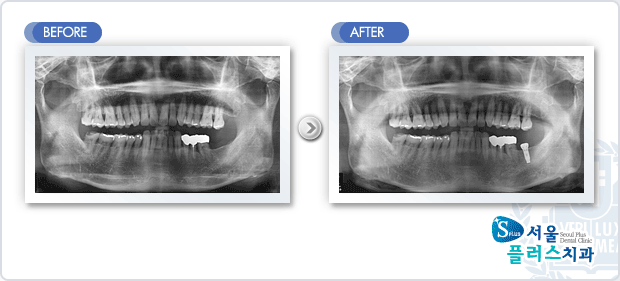

[임플란트] 임플란트 - 하악 구치부 상실부위 임플란트 식립